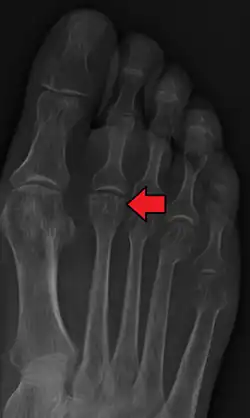

Diagnosis

Accurate diagnosis of Freiberg disease typically involves a combination of clinical examination and imaging studies:

- Physical examination: Assessment of pain, swelling, and range of motion in the affected foot.

- Radiography: X-rays may reveal flattening, sclerosis, or fragmentation of the metatarsal head.

- Magnetic Resonance Imaging (MRI): Provides detailed images of soft tissue and bone changes, particularly useful in early stages of the disease.